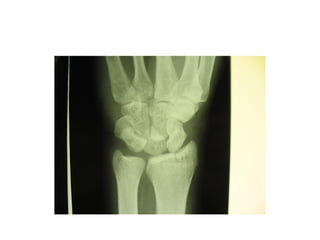

This document discusses several cases of scaphoid fractures in different patients. A 42-year-old female presented with carpal tunnel syndrome and wrist pain after a fall and was found to have a large cyst and fracture in her scaphoid bone. A 16-year-old male reported four months of painful wrist after a skateboarding injury. Imaging also showed a non-union in the wrists of a 42-year-old man bilaterally. Surgical treatment including open reduction and internal fixation with bone grafting was performed in some cases.